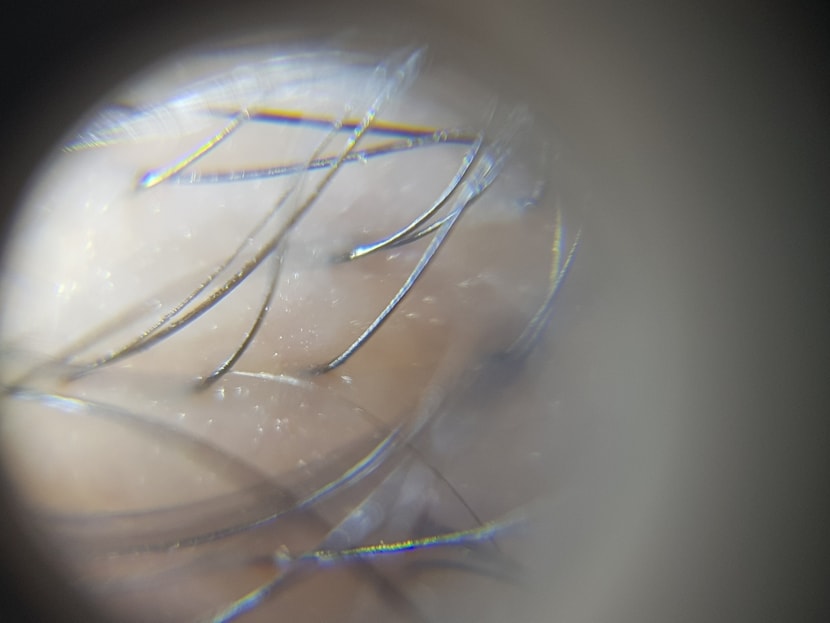

[非切开设计 第1~7天后记] 从小额头宽,头发薄,所以有自卑感,但是连续5年服用非那斯特里德,感觉渐渐只剩下绒毛了,所以决定现在只剩下不好的事情了。 医院的决定是因为看到同事做的手术,在密度、不尴尬的设计、管理等多方面看到了值得信赖的部分,所以没有太苦恼地选择了。 手术是用非切开微创手术进行的,据说麻醉注射最疼,我在睡眠状态下进行,完全不知道疼就结束了。 医护人员也很亲切,所以放松了紧张,收到了。 第二天为了洗发水再次去了医院,但是细心告诉我管理方法,所以很开心。 照片也是这个时候拍的照片。 几乎没有浮肿或疼痛,直到第7天的现在,睡觉时只是有点在意翻来覆去,没有不舒服的地方。 除了费用以外,没有其他不便的手术... 好像是对的。 因为是白领,所以即使复职3天左右,工作也不会有负担。 我休了周四和周五的假,第5天第一天上班,还不错。 希望以后能站稳脚跟?????